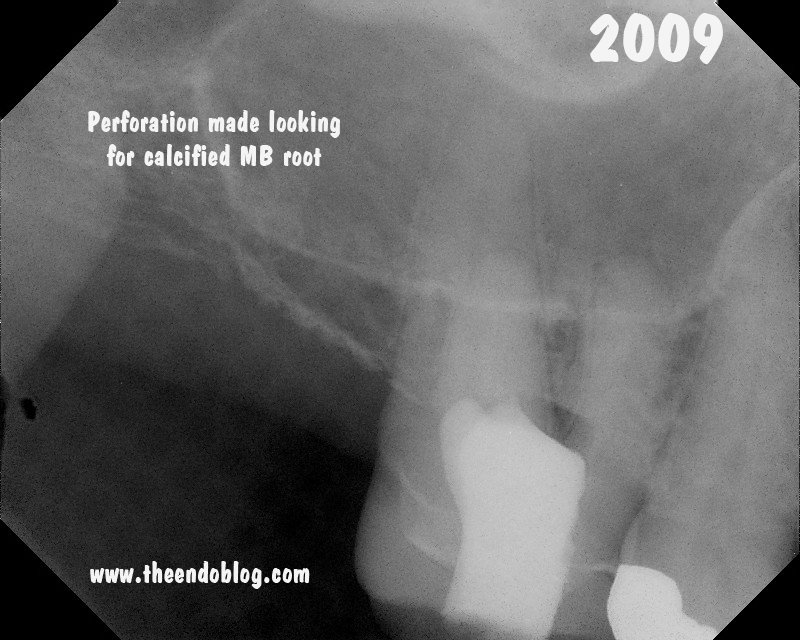

This patient came to Superstition Springs Endodontics

in June 2009. Her general dentist had started RCT on #3 but was unable

to locate the MB canal(s). A perforation was made during the efforts